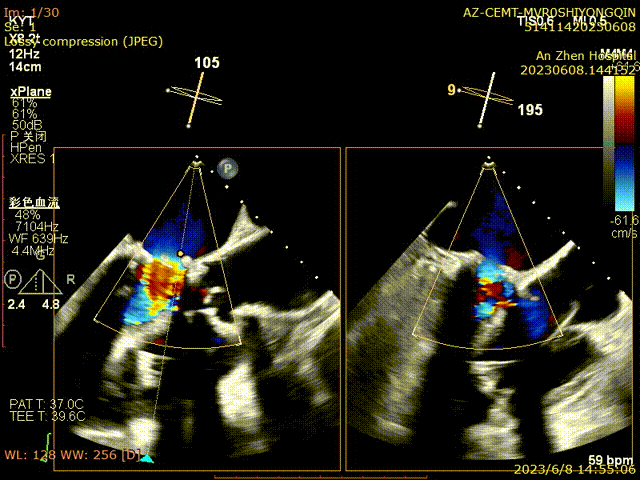

二尖瓣瓣叶增厚、毛糙、闭合欠佳,PHT法测二尖瓣人工生物瓣口积:1.2cm2,cw估测二尖瓣瓣口平均跨瓣压差:8mmHg,CDFI:收缩期二尖瓣房侧见中量反流信号,最大反流面积约5.0cm2。三尖瓣缘轻度增厚,前叶及隔叶见可见关闭裂隙约3mm。CDFI:收缩期三尖瓣房侧见大量反流信号,反流面积11.1cm2,TRVmax:3,27cm/s,PG:43mmHg,TI法估测SPAP:53mmHg

患者全麻,摆体位可寻找衰败生物瓣的切线投照体位,后消毒铺巾,穿刺双侧股静脉,左侧股静脉植入临时起搏器,右侧股静脉作为主入路,在超声指引下,按术前CT评估要求穿刺房间隔到达左心房,肝素化后(ACT>250秒),导入Agilis可调弯鞘管到达左心房,Pig造影导管跨过二尖瓣到达左心室心尖部,导入Safari导丝到达左心室;以12×40mm球囊扩张房间隔确认SAPIEN 3瓣膜可通过后,导入反向安装的23mm+3ml瓣膜到达下腔静脉,组装成功后,翻转其调弯系统后送入到左心房,跨过衰败的二尖瓣,在切线投照体位定位精确后,快速心室起搏下释放瓣膜,见瓣膜位置良好,超声显示无瓣周漏,测量左心室和桡动脉压差稍增高,超声显示LVOT流速稍增快;撤出瓣膜输送系统及导丝,撤出临时起搏电极,局部加压包扎,患者清醒后安返病房。

术前食管超声检查确认人工二尖瓣衰败,重度关闭不全

术后超声评估无反流